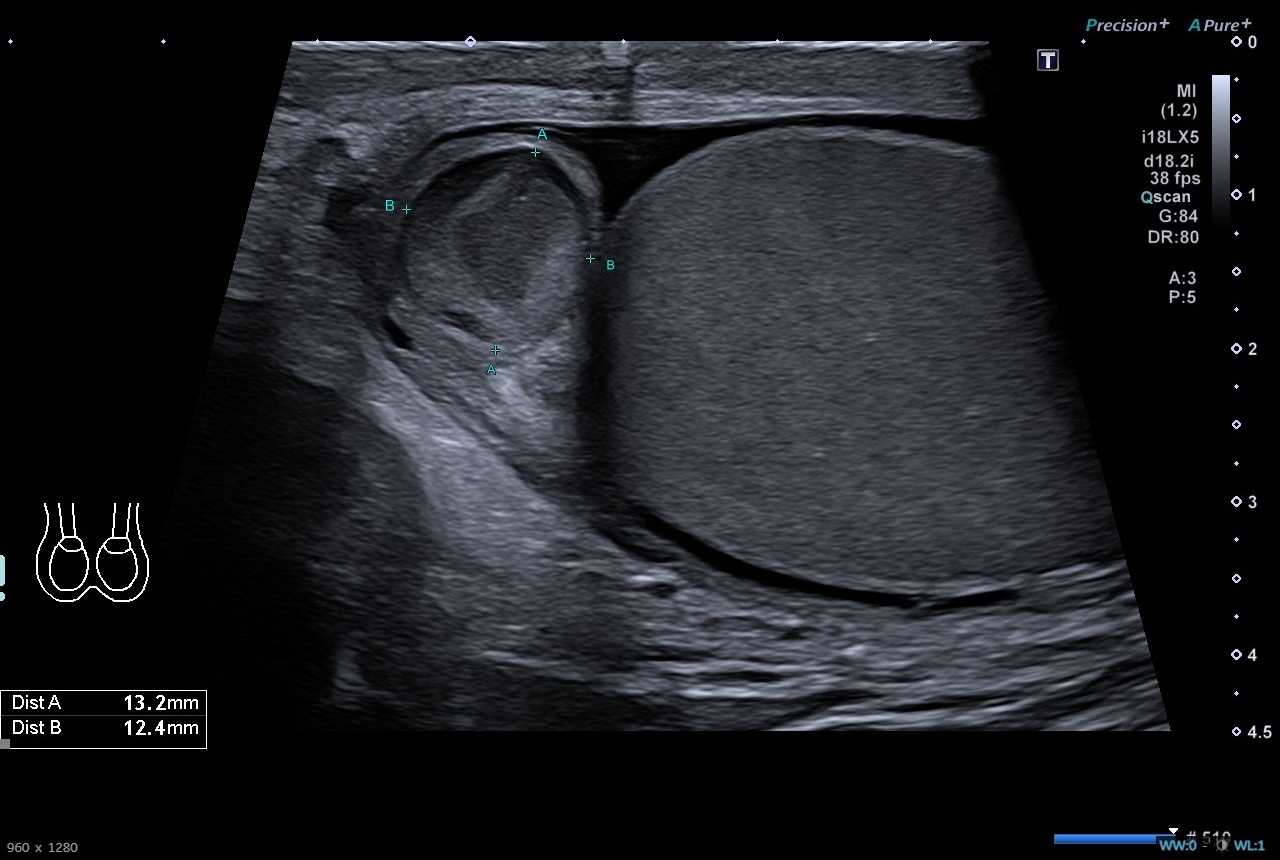

Pruebas complementarias: Sistemático de orina negativo. Ecografía escrotal: Testículos, epidídimos y cordones espermáticos de tamaño, morfología y ecogenicidad normales. Doppler normal en ambos testículos. Adyacente al polo superior del testículo derecho se identifica una estructura redondeada de unos 13 x 12 mms de ecogenicidad heterogénea, sin captación Doppler interna. Es sugestivo de torsión de hidátide de Morgagni, a correlacionar con evolución clínica. No hay datos de torsión testicular. Presencia de moderado hidrocele de aspecto reactivo.